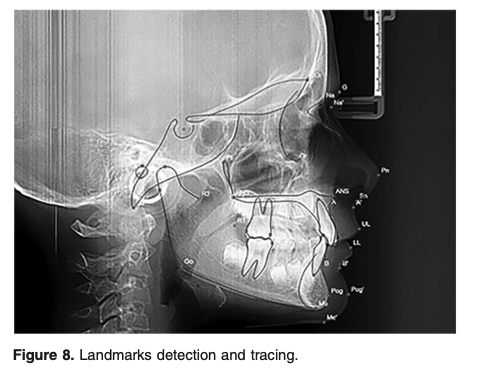

Foi um ensaio controlado randomizado, de centro único. Os participantes eram crianças entre 9 e 12 anos com mordida profunda e padrão esquelético hipodivergente. A amostra foi dividida em dois grupos: (1) grupo AU composto por pacientes com AUs com elásticos intermaxilares posteriores e (2) grupo FABP como controle. Os desfechos foram variáveis esqueléticas e dentoalveolares em radiografias cefalométricas.

Um total de 28 pacientes (13 meninos, 15 meninas) com idade média de 10,66 anos foram incluídos. A duração do tratamento foi de 8,16 meses no grupo UA e 7,22 meses no grupo FABP. Após o tratamento, o ângulo entre a base anterior do crânio e a mandíbula no plano vertical aumentou significativamente (P = .000) em ambos os grupos (cerca de 1,97 graus no grupo UA e 2,75 graus no grupo FABP). A sobremordida diminuiu significativamente em ambos os grupos ( CU 2,1 m no grupo UA e 3,64 m no grupo FABP), mas diminuiu menos significativamente no grupo UA do que no grupo FABP. Os incisivos superiores se extruíram significativamente após o tratamento com ambos os aparelhos (6,6 graus no grupo AU e 5,9 graus no grupo FABP).